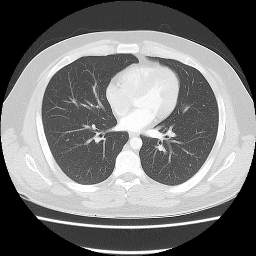

Ground truth

Refer to captionRefer to caption

FUTON (ours)

PSNR=29.18 dB

WIRE

PSNR=27.80 dB

Gauss

PSNR=25.90 dB

SIREN

PSNR=24.59 dB

ReLU+PE

PSNR=23.17 dB

Figure 9: Comparison on sparse-view CT reconstruction. FUTON produces clearer anatomical structures with reduced streak artifacts from 150 projection angles. The CT scan is taken from Radiopaedia and downsized to 256×256256{\times}256 resolution.

5.3.3 CT Reconstruction

CT reconstruction recovers 2D slices from Radon transform projections. We evaluate on a chest CT from Radiopaedia downsized to 256×256256{\times}256, simulating 150 projection angles uniformly over 180180^{\circ} (sparse-view protocol). We optimize in the sinogram domain, minimizing Radon=(𝒔)(𝒔^)2\mathcal{L}_{\text{Radon}}=\left\lVert\mathcal{R}(\bm{s})-\mathcal{R}(\hat{\bm{s}})\right\rVert^{2}, where \mathcal{R} is the Radon transform, ensuring reconstruction-projection consistency. We employ weight decay regularization with λ=4×103\lambda=4{\times}10^{-3} for FUTON and all baselines to prevent overfitting and train for 4000 epochs to allow sufficient convergence.

As shown in Figure 9, FUTON (with R=K=256R=K=256) achieves a PSNR of 29.18 dB, exceeding WIRE by 1.38 dB and outperforming Gauss (25.90 dB), SIREN (24.59 dB), and ReLU+PE (23.17 dB). FUTON produces clearer anatomical structures with reduced streak artifacts (characteristic of limited-angle tomographic reconstruction) and better-delineated lung and mediastinal structures. These results indicate effectiveness beyond natural images, with potential for computational imaging and medical diagnostics where reducing radiation dose while maintaining quality is paramount.